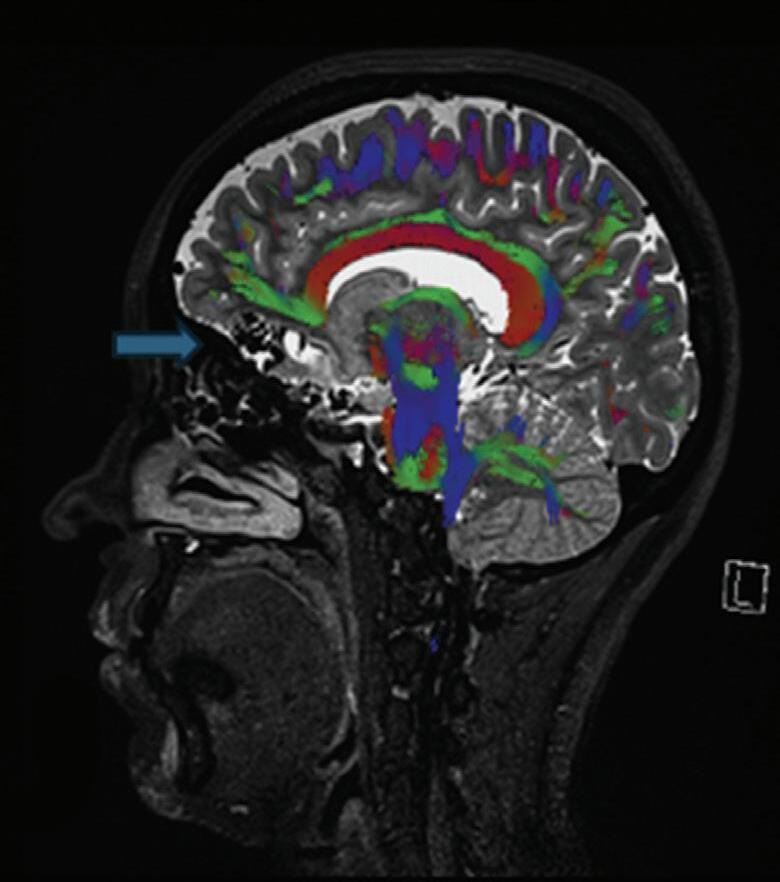

Fig. 1-8. (a-c) RNM T1 com contraste, cortes sagital (a), coronal (b) e axial (c) demonstrando MAV não rota com nidus localizado no lobo occipital à esquerda (setas longas). (d) Arteriografia digital cerebral com injeção de contraste via carótida direita (AP) mostrando a contribuição da carótida direita na irrigação da MAV contralateral. (e,f) Com injeção de contraste via carótida esquerda, em Perfil e AP respectivamente, observa-se nidus compacto nutrido por ramos da artéria cerebral média à esquerda e a veia de drenagem precoce se dirigindo para o seio sagital superior. Projeções em AP (g) e em perfil (h) demonstrando a contribuição do sistema vertebrobasilar por meio de ramos distais da artéria cerebral posterior à esquerda e drenagem para os seios sagital superior e sigmoide à esquerda (setas curtas).

Fig. 1-9. RNM T2 em cortes (a) axial e (b) sagital. (c,d) Tractografia axial – sagital, demonstrando a posição de uma MAV não rota localizada na superfície basal do lobo frontal, nos giros orbitários e reto à direita (setas longas). Arteriografia digital cerebral com injeção de contraste via carótida direita, (e) AP e (f) em perfil demonstrando MAV nutrida por ramos da artéria cerebral média e cerebral anterior direita e drenagem para o seio sagital superior (seta curta).